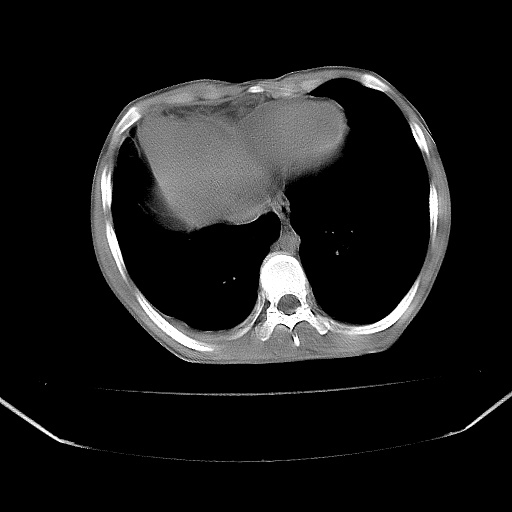

以下是引用zjzjr在2008-7-20 12:57:00的发言:[br]考虑为生殖源性肿瘤(内胚窦瘤),侵袭性胸腺瘤可能性大;右侧少量胸腔积液。

以下是引用xinliheng001在2008-7-20 21:17:00的发言:[br]右纵隔巨大分叶状软组织均质密度肿块,右上肺叶受压明显,纵隔右移、胸膜受累有少量积液和结节样增厚。应增强扫描一定会有更具诊断价值的信息。

以下是引用xinliheng001在2008-7-20 21:17:00的发言:[br]右纵隔巨大分叶状软组织均质密度肿块,右上肺叶受压明显,纵隔右移、胸膜受累有少量积液和结节样增厚。应增强扫描一定会有更具诊断价值的信息。